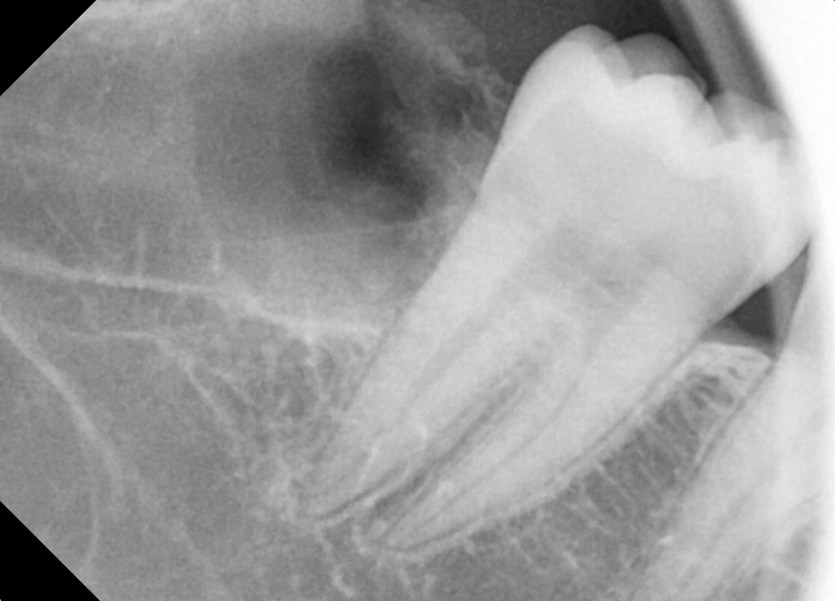

#38,48 사랑니 발치

구강 외과 전문의가 당일 발치했습니다.